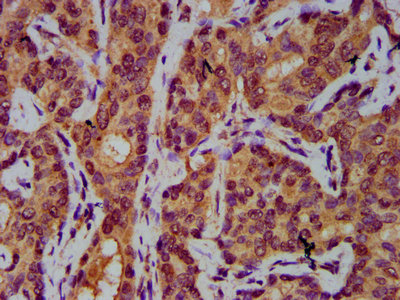

IHC image of CSB-PA883373LA01HU diluted at 1:400 and staining in paraffin-embedded human liver tissue performed on a Leica BondTM system. After dewaxing and hydration, antigen retrieval was mediated by high pressure in a citrate buffer (pH 6.0). Section was blocked with 10% normal goat serum 30min at RT. Then primary antibody (1% BSA) was incubated at 4°C overnight. The primary is detected by a biotinylated secondary antibody and visualized using an HRP conjugated SP system.